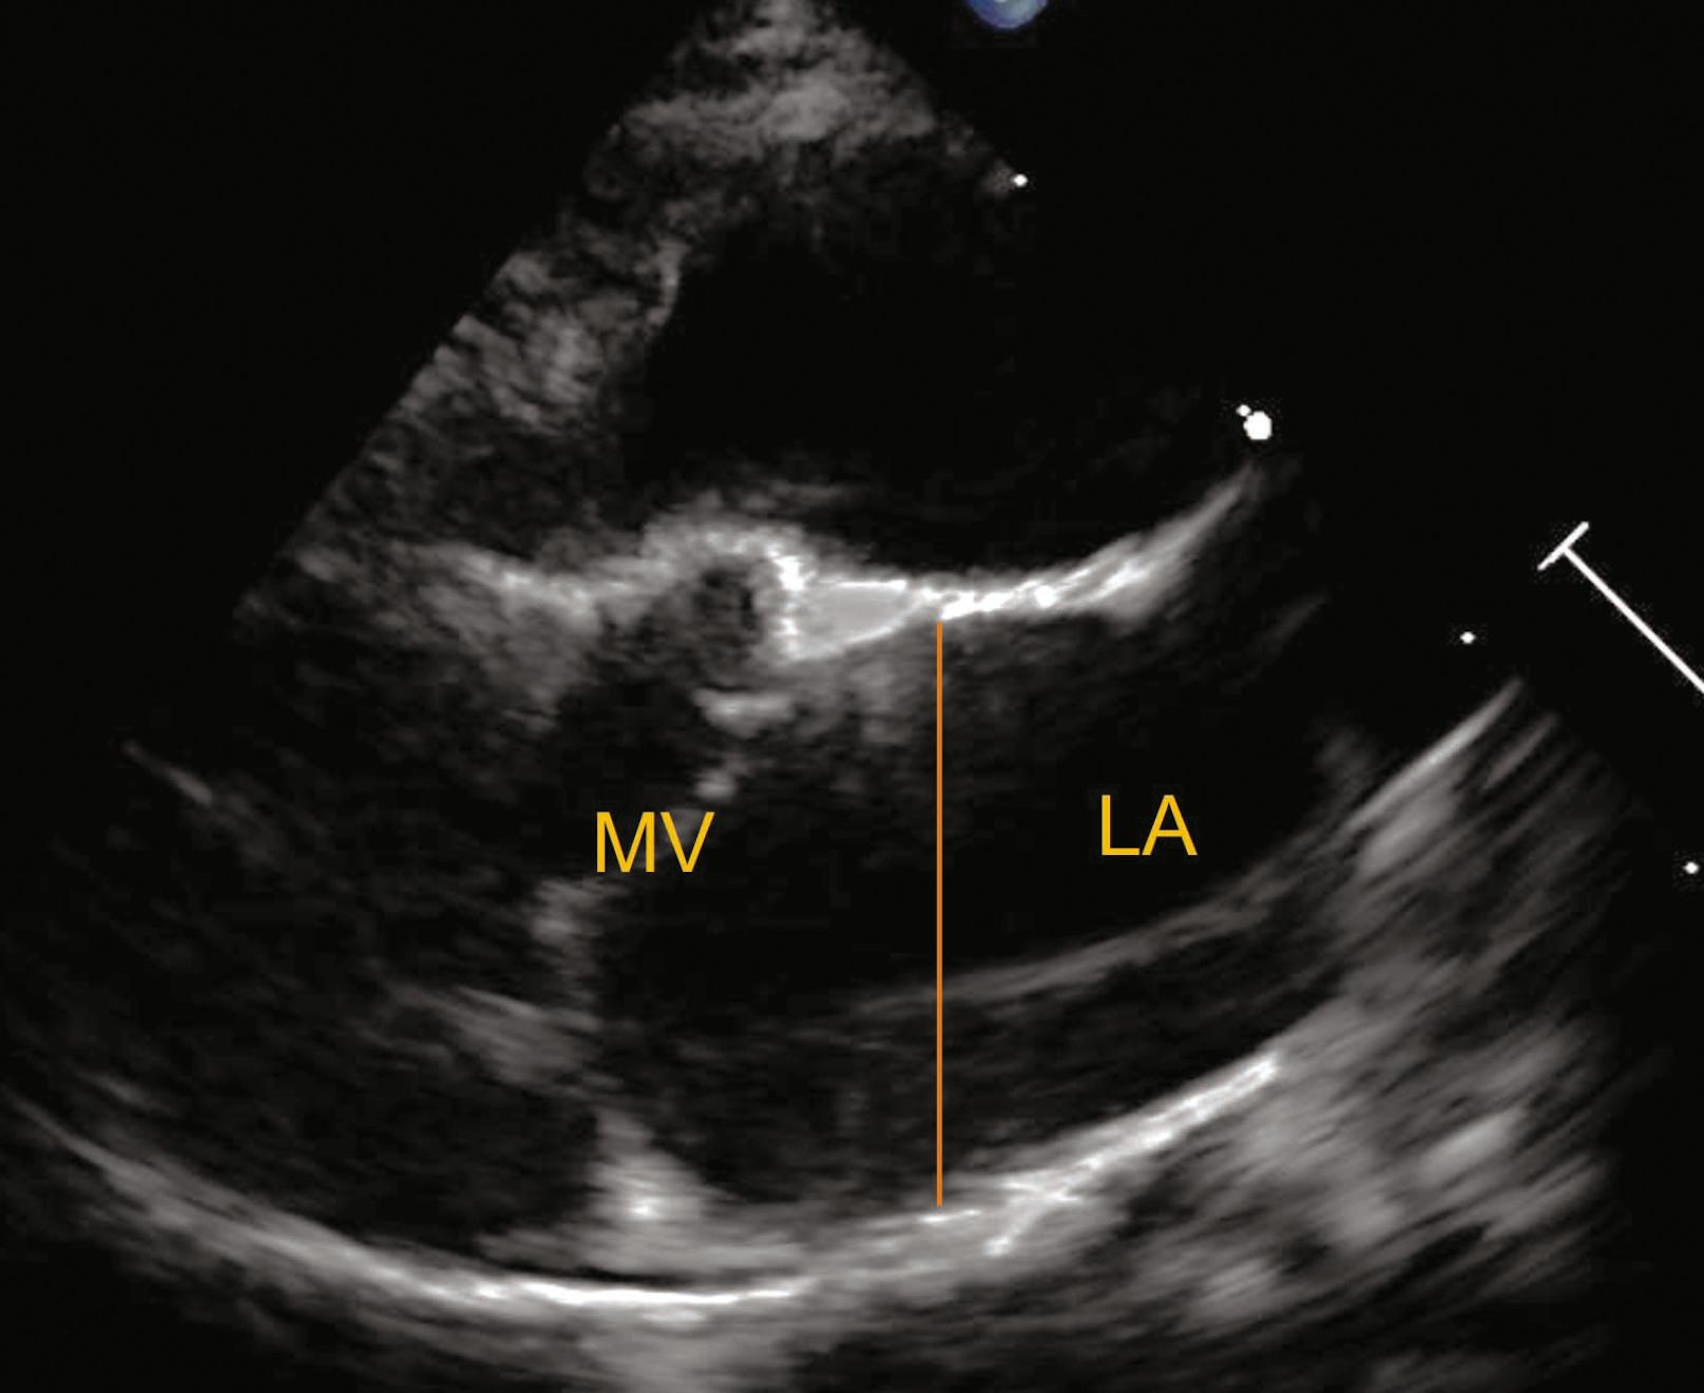

Source: parcamifc.pages.dev Cardiomyopathie hypertrophique féline au stade , Microscopiquement, le tissu cardiaque se désorganise suite à la mort des cellules myocardiques (30 à 60% des chats, 90% chez l'Homme et le. La cardiomyopathie hypertrophique du chat est une pathologie primaire fréquente qui se caractérise par un épaississement du myocarde

Source: eatimelyonb.pages.dev Cardiomyopathie Hypertrophique (CMH) Hôpitaux Universitaires Pitié Salpêtrière , La cardiomyopathie hypertrophique chez le chat est une maladie grave nécessitant une surveillance étroite et un traitement adapté Cardiomyopathie hypertrophique (CMH) chez le chat QU'EST-CE QUE LA MYOCARDIOPATHIE FELINE (CMH) La myocardiopathie hypertrophique, aussi appelée cardiomyopathie hypertrophique est souvent désignée par les initiales CMH ou MCH

Source: seviyogbd.pages.dev Prise en charge du chat insuffisant cardiaque Royal Canin , La CMH est une maladie caractérisée par un épaississement anormal du muscle cardiaque et peut être d'origine primaire ou secondaire La cardiomyopathie primaire est diagnostiquée lorsqu'une cause sous-jacente ne peut être identifiée